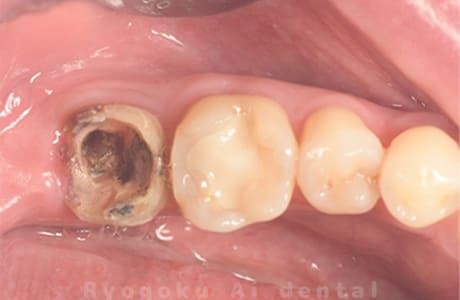

根充断面1

根充断面2

根充断面3

- 原因

- 急性歯髄炎

- 治療内容

- マイクロエンド治療

- 治療費用

- 99,000円

- 担当医

- Dr. 炭野

急性歯髄炎の患者様に、マイクロエンド治療を行いました。

<リスク・副作用>

術後は痛み、腫れ、痺れなどの副作用が生じる場合があります。症状が再発する可能性があります。